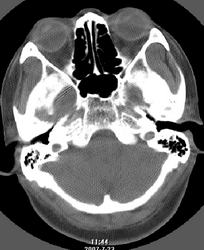

以下是引用还珠格格在2007-7-31 19:32:00的发言:[br]右侧鼻前庭内可见软组织块影,部分鼻中隔包绕其内,邻近骨质未见明显吸收破坏,考虑 1、鼻息肉可能性大 内翻乳头状廇不除外。期待结果。

以下是引用zjzjr在2007-7-31 20:29:00的发言:[br]右侧鼻前庭内可见软组织块影,部分鼻中隔包绕其内,邻近骨质未见明显吸收破坏,考虑 1、鼻息肉可能性大 内翻乳头状廇及肉芽肿类病变除外。期待结果。